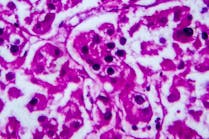

Although A20 analysis is not currently performed in the clinical setting, it is an emerging biomarker with the potential to augment the analysis of novel (engineered) host-pathogen interaction. Since the clinical laboratory is essential to the detection of unusual pathogens in the patient population, this may be the ideal environment for the detection of overt A20 modulation. While there are several methods which can be used to monitor A20 activity, immunohistochemistry is the most attractive. This is due to the fact that immunohistochemistry allows direct visualization of the protein and requires no prior knowledge of how A20 modulation may have been achieved. Normally A20 tends to localize into discrete punctate structures in the cytoplasm.7 These structures have been visualized with the aid of fluorescently-tagged antibodies. Such antibodies can be used to determine whether A20 is present in clinical samples, whether it is under-expressed or over-expressed, and possibly to determine whether it is properly localized. In addition, antibodies can be developed to target individual A20 domains. This will make it possible to determine whether an organism is expressing a specific domain, if a specific domain from endogenous A20 has been re-targeted, or whether A20 has been cleaved by an anti-A20 enzyme resulting in a separation of the domains.